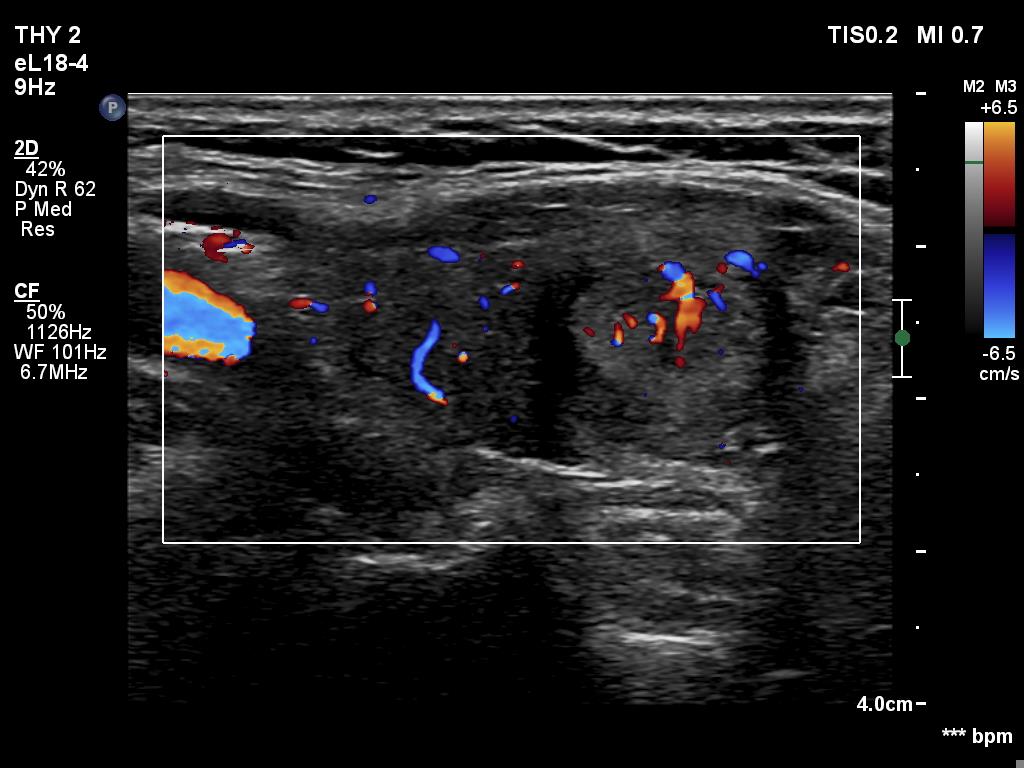

TIRADS - case 294 (ultrasonographic picture 10)

Left lobe, longitudinal scan, color Doppler mode. The vascularity is not specific.